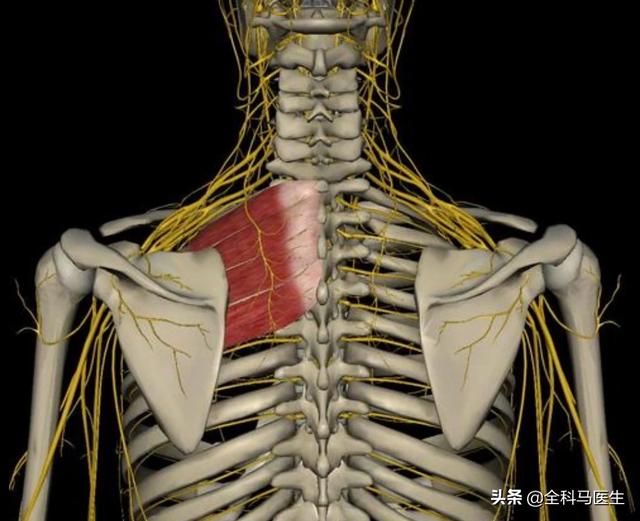

Comme indiqué ci-dessus, ce muscle est anatomiquement ce que l'on appelle un "levator scapulae (anatomie)". Il se développe d'une part sur l'apophyse transverse des vertèbres cervicales 1 à 4, et d'autre part à l'endroit même où se trouve le point douloureux (l'angle supérieur interne de l'omoplate). Sa fonction principale est la suivante :Lorsque la fin du point de douleur est fixéeLa tête et le cou sont inclinés vers l'arrière lorsque les deux côtés sont contractés et raccourcis.Lorsque la tête est baissée pendant une longue période, elle s'étire progressivement lorsque la tête est tirée vers l'avant, jusqu'à ce qu'à la limite, lorsqu'il n'est plus possible de l'étirer davantage, il y ait une douleur à l'angle supérieur interne de l'omoplate, à l'extrémité stationnaire.。

2) Deuxième raison : bien que rares, lesFacilement mal diagnostiquéC'est le problème des releveurs de l'omoplate décrit plus haut. Une autre structure importante est le muscle oblique postérieur, comme indiqué ci-dessous :